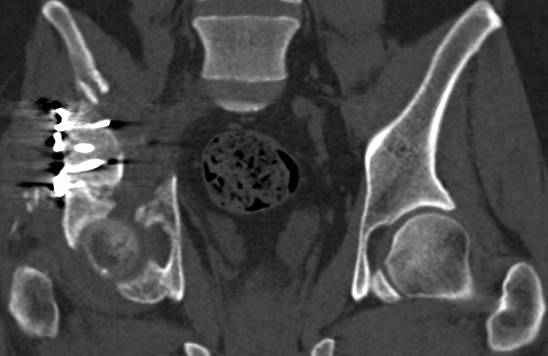

Re: перелом правой половины таза

высылаю дополнительно сканы.